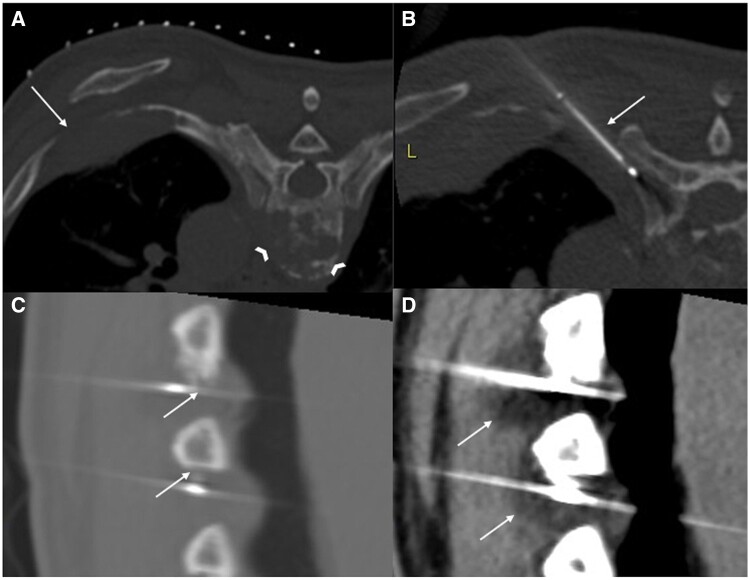

Abstract Image